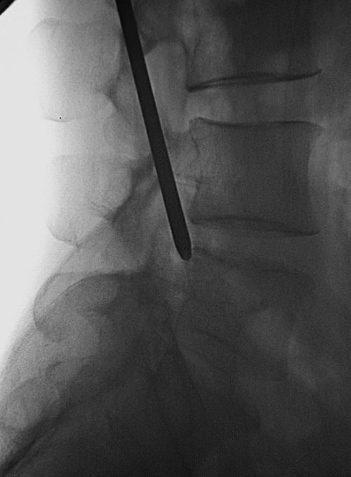

上关节突尖的稍背侧(图11):0.5%利多卡因局麻后用勺状针由穿刺点与额状面呈20°缓缓进针,边进针边注入局麻药,达上关节突尖的稍背侧,抵骨,注入局麻药10ml。

图11 勺状针针尖抵达上关节突尖的稍背侧A.前后位透视;B.侧位透视

上关节突尖的腹侧(图12):调整勺状针的勺状面向腹侧,稍加大穿刺角度,使针尖略向腹侧进针,滑过上关节突尖部进入椎间孔,注入局麻药3ml。

图12勺状针针尖抵达上关节突尖的腹侧A.前后位透视;B.侧位透视